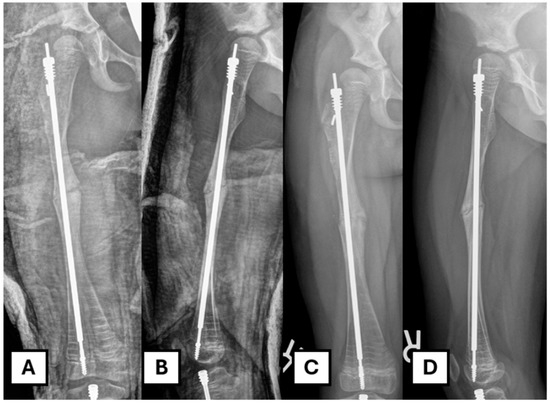

The patient is admitted overnight for pain control. Two doses of post-operative prophylactic antibiotics are administered. A standard AP and lateral X-ray of the operated femur is obtained on day one post-op. The patient remains non-weight-bearing on the operated leg for six weeks post-op. A follow-up in the clinic is performed two weeks after the initial visit, at which point the wound is reviewed. A decision is made regarding the progression of weight-bearing status when the X-ray shows adequate healing (Figure 6).

Figure 6. Post-operative image after revision. (A,B) Immediate post-operative radiograph. (C,D) Six weeks post-operative radiograph showing progression of osteotomy site healing.